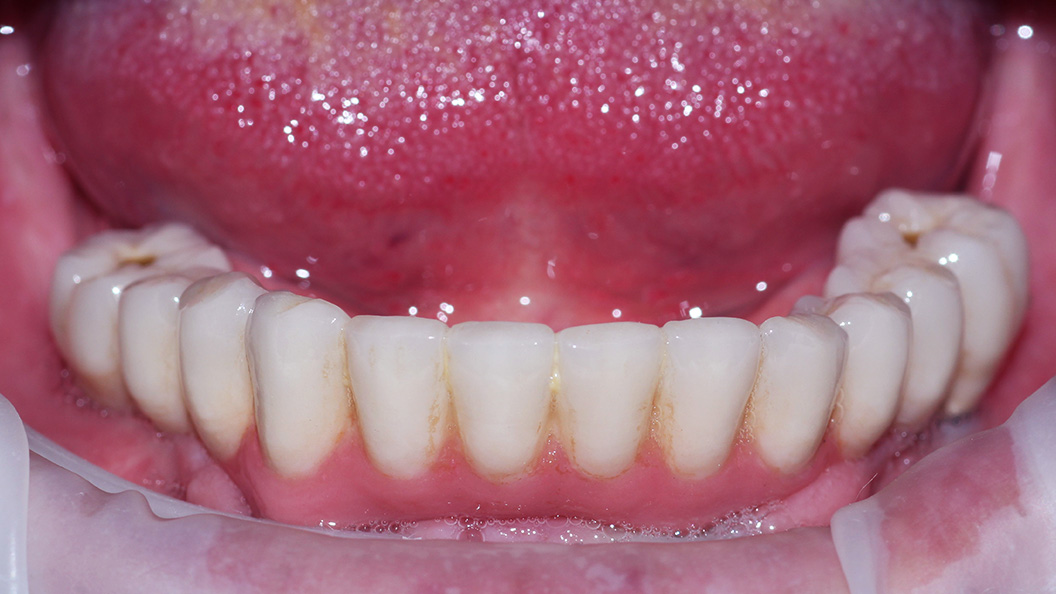

До и после лечения

В нашу клинику обратился пациент с жалобами на полное отсутствие зубов на нижней челюсти.

Осмотр проводил врач стоматолог-ортопед и хирург Мельников Алексей Владимирович. После консультации, совместно с пациентом, было решено провести протезирование по технологии All-on-4.

Методика позволяет восстановить зубной ряд на 4-х имплантах, установленных по определённой технологии. Протез при этом фиксируется сразу после имплантации.